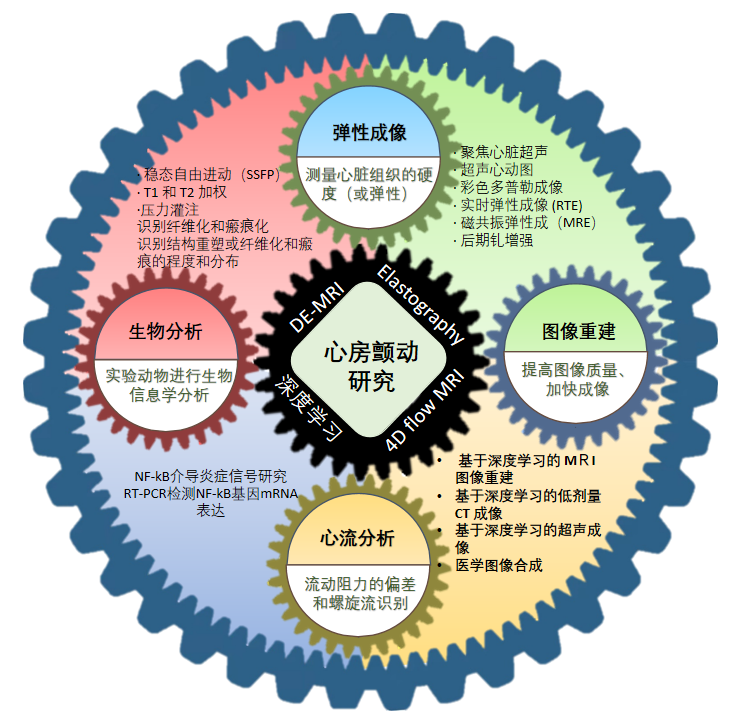

心房颤动(atrial fibrillation,AF)是临床常见的心律失常之一,具有较高的致残率和致死率。目前为止,影响因素的多样性和测试方式的差异性,导致我们很难理解心颤真正的机制和原理。那么,我们在科学上应该如何探讨这个研究?本项目主要由中国科学院深圳先进技术研究院的Kelvin Wong研究员团队与四川大学华西医院的朱达医师的团队合作开展,研究内容框架如图1所示。

图1 齿轮架构图为Kelvin Wong团队研究内容框架